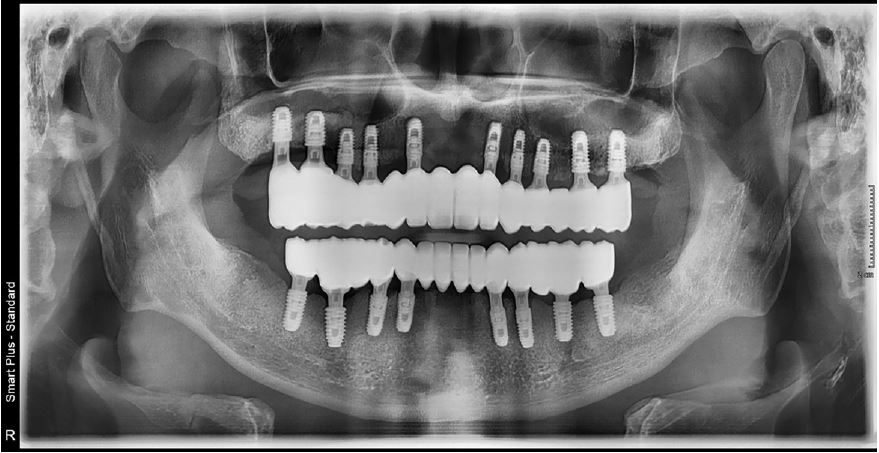

As a result, the following treatment plan was established: (a) extraction of the remaining teeth in the maxilla and mandible, and (b) implant placement using implant surgical guides. Specifically, a total of 10 implants were planned to be placed at the maxillary lateral incisors, canines, first premolars, first molars, and second molars on both sides, whereas a total of eight implants were planned to be placed at the mandibular canines, first premolars, first molars, and second molars on both sides. Subsequently, it was decided to wait for healing after delivering provisional dentures to the upper and lower jaws. The final prosthesis was designed with three pieces, including one anterior segment and two posterior segments, on both upper and lower jaws.

During implant surgery, an implant surgical guide was placed on both sides of the canines before extraction of the remaining mandibular canines. Up to this procedure, all implants required for the patient, except canines, were completed successfully (TS-III; OSSTEM, Seoul, Korea). After the extraction of canines on both sides, which were used as supporting components (i.e., anchor teeth) for the implant surgical guide, a second-step implant surgical guide was used to place the implants on the canine areas immediately (Fig. 8A). In addition, provisional dentures were delivered after the surgical procedures. Similar to the mandibular surgery, after the extraction of the supporting teeth for the implant surgical guide, a second-step implant surgical guide was used to place the implants immediately after the extraction (Fig. 8B). Finally, provisional dentures were stably delivered after the surgical procedures. After a 2-month osseointegration period, implant failure was observed in the right mandibular first molar, therefore, the fixture was removed and re-surgery was performed in that area. However, provisional fixed restorations were made using custom abutments and 3-piece polymethylmethacrylate (PMMA) for other successfully healed areas (Fig. 9).

The treatment was completed without any discomfort after delivery of the final prosthesis because the vertical dimension or occlusal surface shape of the prosthesis was exactly the same as that of the provisional prosthesis (Figs. 10 and 11).